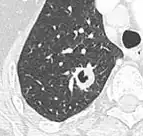

- Location: Upper lobe location is a risk factor for cancer, while a location close to a fissure or the pleura indicates a benign lymph node,[8] especially if having a triangular shape.[9]

- Margin morphology: a spiculated margin is a risk factor for cancer.[8] Benign causes tend to have a well defined border, whereas lobulated lesions or those with an irregular margin extending into the neighbouring tissue tend to be malignant.[10] In particular, spiculations are highly predictive of malignancy with a positive predictive value up to 90%.[9] Also, a "notch sign", which is an abrupt indentation of the nodule, increases the risk of cancer, but may also be found in granulomatous diseases.[9]

-

subpleural nodule.[9] -

Round well-delineated solid lung nodule with smooth border.[9] -

Lobulated nodule.[9] -

Spiculated lung nodule.[9] -

A "notch sign".[9] -

A triangular perifissural node can be diagnosed as a benign lymph node.[9]